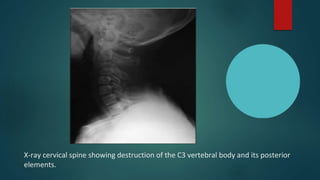

X-ray cervical spine showing destruction of the C3 vertebral body and its posterior

elements.

X-ray cervical spineshowing destruction of the C3 vertebral body and its posterior elements.